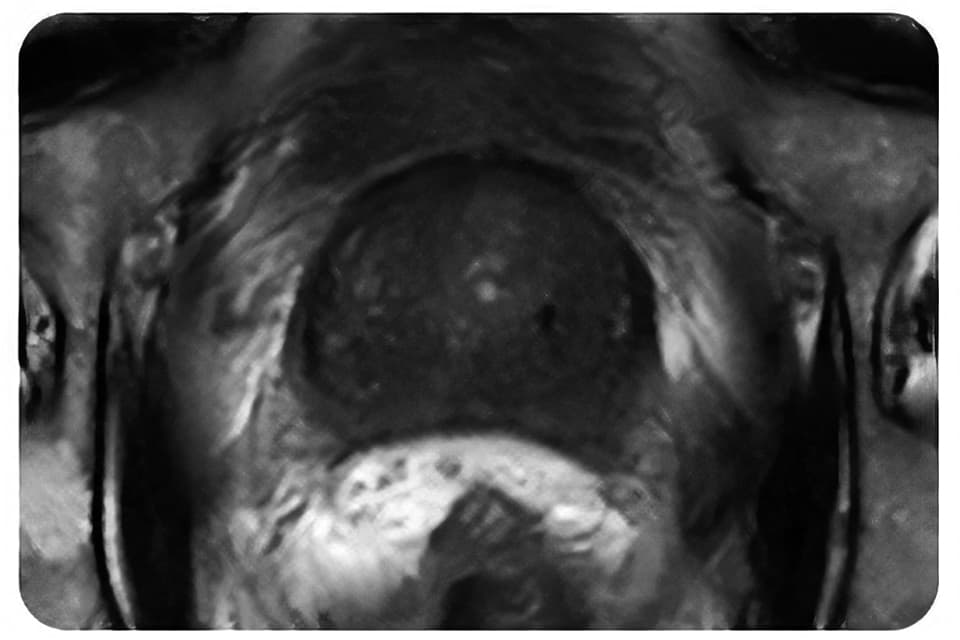

MRI

各種画像診断モダリティ(CT、CBCT、kV-X線、MRI、超音波)での明瞭な可視性があります。

Gold Anchorマーカの特徴-3 優れた可視性

Gold AnchorマーカはMRI装置における可視性の向上をはかるため、99.5%の金と0.5%の鉄の合金としています。